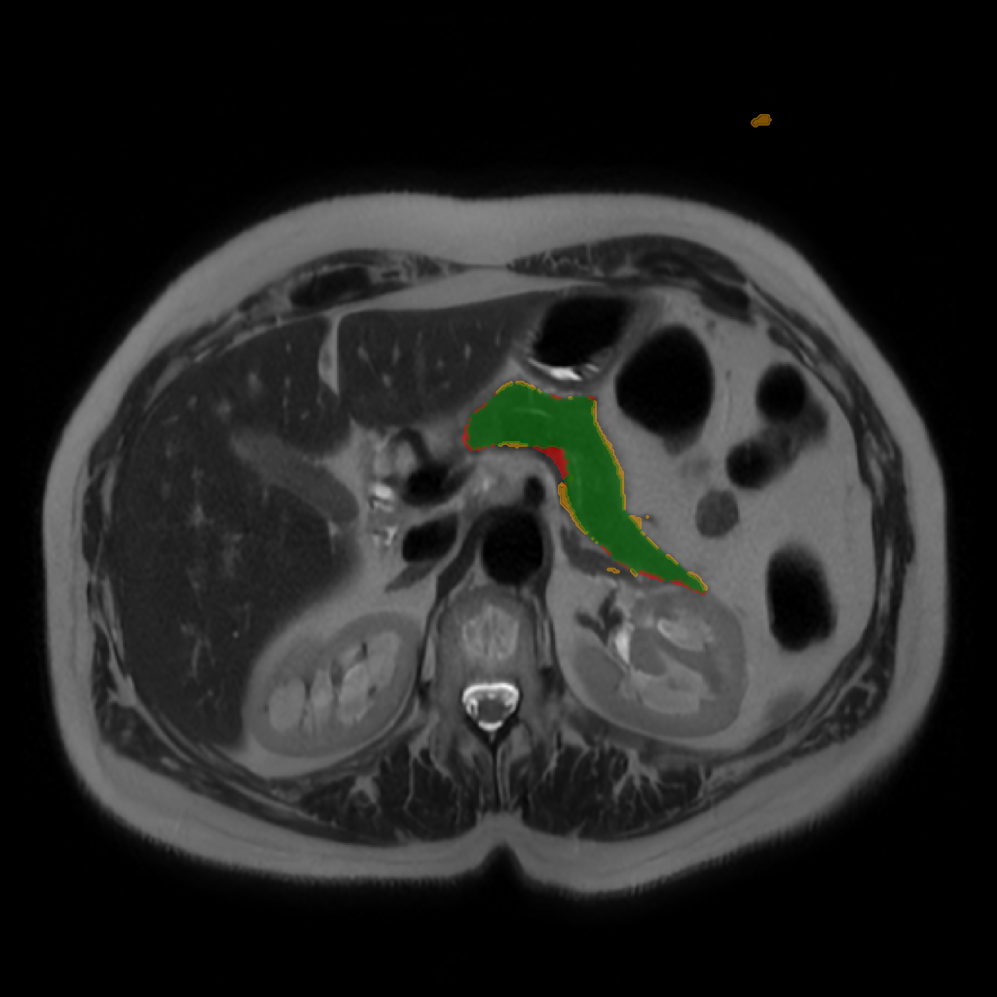

Accurate pancreas segmentation is a critical prerequisite for precise cyst analysis and classification. Recently, we developed PanSegNet [zhang2025large], a novel segmentation architecture incorporating linear self-attention layers [zhang2022dynamic] within the nnUNet framework [isensee2021nnu] to enhance global information modeling capabilities while maintaining computational efficiency (Fig. 1). PanSegNet demonstrated exceptional segmentation performance across both T1W and T2W modalities, achieving mean dice scores of 86.817.30% and 89.626.38%, respectively (Table 1, Fig. 2b-c). This performance significantly exceeded that of Swin-UNETR [hatamizadeh2021swin], one of the most used state-of-the-art transformer-based medical segmentation models, which achieved dice scores of 79.091.40% and 76.290.66% for T1W and T2W, respectively (). In this study, we integrated PanSegNet into our Cyst-X engine along with a classifier for risk prediction. In Section 2.2, we show that the choice of segmentation model affects the classification results. The performance advantage of PanSegNet was consistent across all seven medical centers, demonstrating robust generalization despite variations in imaging protocols and equipment (Table 1). This cross-institutional reliability is particularly important for clinical applications, where model performance must remain consistent regardless of imaging site or acquisition parameters.

Each patient was categorized into one of these three ground truth classes: no risk/control, IPMN low-risk, or IPMN high-risk. To evaluate variability in image acquisition, we applied uniform manifold approximation and projection (UMAP) to image quality indicators, revealing distinct clustering patterns by imaging center and slice thickness. This heterogeneity reflects real-world clinical variability, enhancing the dataset’s generalizability while presenting technical challenges for model development. Fig. 6 shows examples of low-grade, high-grade, and cancer developing IPMNs from the Cyst-X dataset.